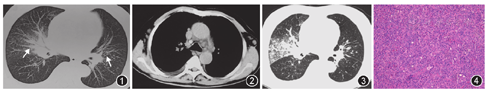

患者男,70岁,因"间断咳嗽、发热3个月"于2018年6月13日入院。患者2018年3月27日因高热1 d伴咳嗽、咳痰于当地医院给予头孢他啶2.0g,2次/d,抗感染3 d无效。于2018年3月30日转至当地三甲医院呼吸科住院,胸部CT示肺部阴影,降钙素原为3.01 μg/L,诊断为"社区获得性肺炎",先后给予左氧氟沙星0.5 g 1次/d、哌拉西林钠他唑巴坦钠4.5 g,2次/d抗感染治疗,症状缓解出院。出院2周后再次出现高热、咳嗽、咳痰,于2018年5月20至2018年6月11日再次入住当地三甲医院呼吸科,先后给予左氧氟沙星0.5 g 1次/d、头孢米诺2.0 g 2次/d、莫西沙星0.4 g 1次/d、比阿培南0.3 g 2次/d、头孢噻肟舒巴坦3.0 g 2次/d抗感染治疗,患者发热及咳嗽症状无好转。2018年6月8日胸部CT示双肺间质改变伴右侧胸腔少量积液(图1,图2)。支气管镜检查提示气管支气管急性炎症改变,BALF普通细菌培养、真菌培养、抗酸染色均阴性。患者抗感染治疗无好转,外院诊断"肺结核并右侧结核性胸膜炎"转诊至我院。

患者为农民,既往健康。体检:体温37.0 ℃,脉搏99次/min,呼吸20次/min,血压133/75 mmHg(1 mmHg=0.133 kPa)。左侧颈部、腋窝可触及数枚花生米大小肿大淋巴结,活动度好,边界清楚,无压痛。皮肤巩膜未见黄染。右下肺呼吸音低,右下肺叩诊呈浊音,双肺未闻及干湿性啰音,心脏及腹部未见异常。入院后血常规示白细胞为6.31×109/L,中性粒细胞为0.57,嗜酸粒细胞为0.17,血红蛋白为118 g/L,血小板为148×1012/L,肝功能、肾功能、电解质均正常,乳酸脱氢酶(lactic dehydrogenase,LDH)为299 U/L,D二聚体正常,ESR为17 mm/1 h,C反应蛋白为30.77 mg/L,降钙素原为0.10 μg/L。PPD阴性,1,3-β-D-葡聚糖(G试验)阴性,半乳甘露聚糖试验(GM试验)阴性,痰涂片抗酸染色阴性3次,痰结核分枝杆菌DNA检测阴性,痰Xpert MTB/RIF未检出结核分枝杆菌核酸,痰真菌涂片阴性,痰真菌培养阴性,痰普通细菌培养阴性,血培养阴性。肿瘤标志物:糖类抗原125为131.20 U/ml,癌胚抗原(CEA)、甲胎蛋白、细胞角蛋白19片段、神经元特异性烯醇化酶、糖类抗原19-9均正常。乙肝表面抗原阴性,丙肝抗体阴性,梅毒抗体阴性,HIV抗体阴性。右侧胸腔积液:李凡他试验阳性,细胞数为1 400×106/L,淋巴细胞为79%,中性粒细胞为21%,总蛋白为34.1 g/L,葡萄糖为6.8 mmol/L,腺苷脱氢酶为19.9 U/L,LDH为179 U/L,细胞学检测可见大量淋巴细胞,未见肿瘤细胞。2018年6月16日复查胸部CT示双肺病变较前有进展(图3)。

入院后于2018年6月15日在局部麻醉下行左侧颈部淋巴结活检术。2018年6月18日病理报告:(左侧颈部)淋巴结(1/1枚)淋巴组织增生性疾病,非霍奇金淋巴结可能(图4)。免疫组织化学检测示CD20(-),PAX-5(-),CD2(+),CD3(+),CD7(+),CD4(+),CD8(+),CD43(+),CD5(+),CD10(LN)(+),BCL-2(+),CD21(+),CD23(+),BCL-6(-),CyclinD1(-),c-myc(-),Mum-1(-),CD30(-),EBER CISH(-),PD1(-),Ki-67(LI约60%)。结合免疫组织化学符合淋巴结血管免疫母细胞T细胞淋巴瘤(angioimmunoblastic T-cell lymphoma,AITL)。骨髓活检可见造血良好,未见淋巴细胞增多及形态异常。最后诊断AITL Ⅳ期肺浸润。

本例患者胸部影像学表现为支气管血管束增粗伴弥漫性结节及磨玻璃影,纵隔淋巴结及左侧腋窝淋巴结增大,右侧胸腔积液。影像学表现支气管血管束增粗伴弥漫性结节常需鉴别的疾病包括癌性淋巴管炎、淋巴瘤、白血病、淋巴增生性疾病、结节病及间质肺水肿等[2]。但是患者外院多次住院均由于发热症状、肺部阴影及降钙素原升高而考虑肺部感染,未注意到影像学提示肺间质受累,且未仔细体检及时发现体表淋巴结从而及时活检明确诊断。回顾本例病例,老年男性、反复发热症状、影像学提示支气管血管束增粗伴淋巴结肿大、血LDH升高应该首先考虑淋巴瘤。而血嗜酸粒细胞升高也为淋巴瘤提示依据,文献报道嗜酸粒细胞升高是淋巴增殖性疾病的一个并发症,有时候甚至为其首发表现。AITL是最常见的嗜酸粒细胞增高相关性疾病,约32%~50% AITL可出现外周血嗜酸粒细胞升高[3]。当临床中遇到反复发热、血LDH升高、胸部影像学提示支气管血管束增粗时需考虑到淋巴瘤可能,如外周血嗜酸粒细胞升高,则需首先考虑AITL。